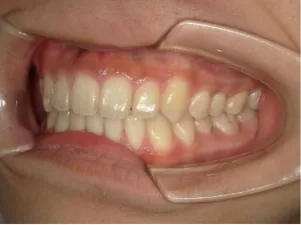

治療後⑤中3:咬合治療終了 マルチブラケット法の期間は9か月

| 行ったご提案・診断内容 | 成長期に行う治療と咬合治療をご提案しました。 成長期治療(成長時期にお口の環境を整え、適正な成長を促す治療)で、 ①歯列弓形態の修正、拡大と前歯を並べる。 ②出っ歯を治す専用の装置を使用する。 ③・MFT:舌や口唇などが正しい動きやポジショニングで機能し、鼻で呼吸できるようにする練習、毎日おうちで習慣づくように続けてもらいます。 ④拡大による顎顔面の適正な成長効果で口元を改善する(写真③)。 |

| 治療のリスクについて | 凸凹(でこぼこ)や口元の突出が残る場合は、抜歯治療へ移行します。 その他、矯正治療に伴うリスクとして、歯ブラシ不足による虫歯・歯周病、装置による違和感・痛み、口内炎、話しにくい・食べにくい、歯肉退縮、歯髄壊死、歯根吸収、顎関節症の悪化などがあります。 |